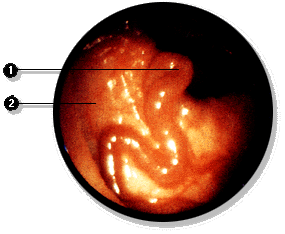

Mediante la esofagoscopía es posible pesquizar várices esofágicas y mediante la rectoscopía es posible pesquizar hemorroides, signos estos dos de hipertensión portal.